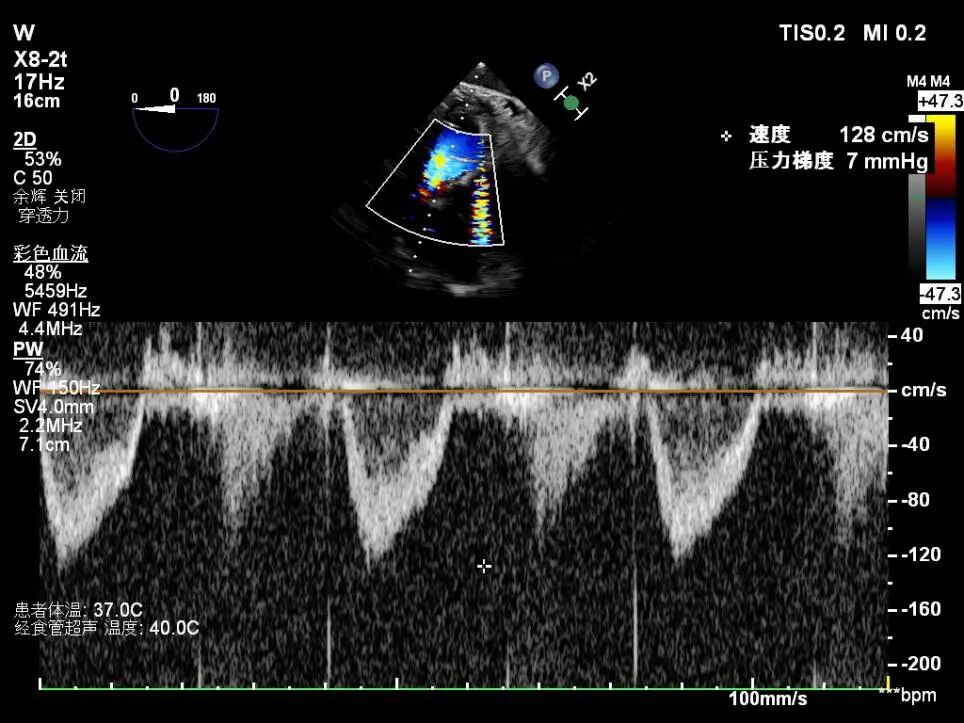

术后TEE图像

瓣膜释放后超声观察无瓣周漏,峰值流速0.76m/s,峰值压差5mmHg,平均压差2mmHg,流出道峰值流速1.28m/s,峰值压差7mmHg。